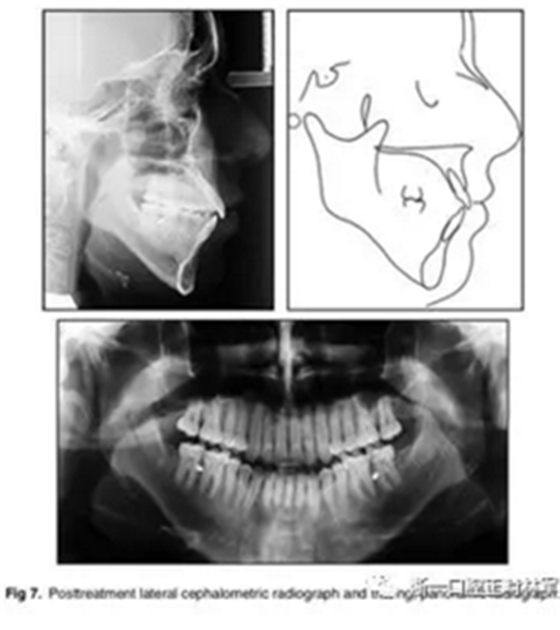

影像學:全景片示:牙根平行度可。頭顱側位片及疊加圖示:下頜骨發(fā)生逆時針旋轉,面部輪廓改善;上切牙轉矩正常,下切牙輕微舌傾;唇突度減小,鼻唇角增大。

治療后50個月:治療結果基本保持穩(wěn)定,左側可見輕微復發(fā)跡象,這可能與患者的TMJ狀況有關,需要進一步治療。